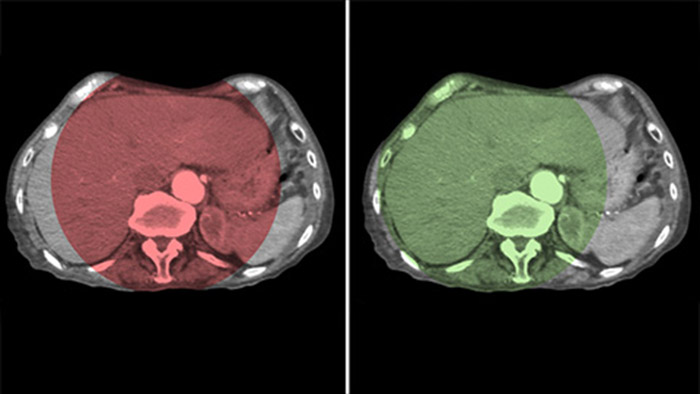

CBCT Dualを使用すると、動脈相の3D画像収集による血管構造と後期動脈相(遅延相)を表示し、造影剤の蓄積状況を一連の操作で視覚化できます。5

Dual Viewでは、2つのCBCTデータセットを同時に表示できます。動脈相と遅延相の両方を並べて表示することも、オーバーレイビューとして1つのフュージョン画像を表示できます。